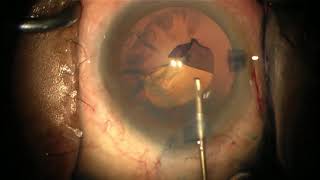

Performing capsulorhexis with a cystotome

Performing capsulorhexis with a cystotome CataractCoach™1782: resident week: cystotome capsulorhexis

Performing capsulorhexis with a cystotome

Performing capsulorhexis with a cystotome CataractCoach™1782: resident week: cystotome capsulorhexis